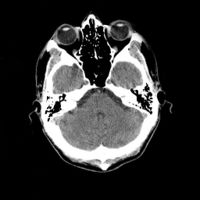

تصوير مقطعي حاسوبي

التصوير المَقْطَعي الحاسوبيX-ray computed tomography نظام تصوير بالأشعة السينية، يُسْتخدم لتصوير مختلف أجزاء الجسم مثل الرأس والقلب والبطن. ويستعين الأطباء بالتصوير المقطعي الحاسوبي على تشخيص الأمراض وعلاجها. وتسمى هذه التقنية أيضًا التصوير المقطعي المحوسب أو التصوير المقطعي المحوري المحوسب.

يمكن للأطباء أن ينظروا داخل جسم المريض عن طريق طلب إجراء مسح للعظام والأوعية الدموية والأدمغة والأنسجة الرخوة بفضل ماسح التصوير المقطعي الحاسوبي (CT). بعد إجراء أول فحص طبي بالأشعة المقطعية للمريض في عام 1971، استخدم أطباء الأشعة عمليات المسح لتشخيص الأورام والصدمات والتخطيط للعلاج الطبي والجراحي والإشعاعي في جميع أجزاء جسم الإنسان تقريباً.